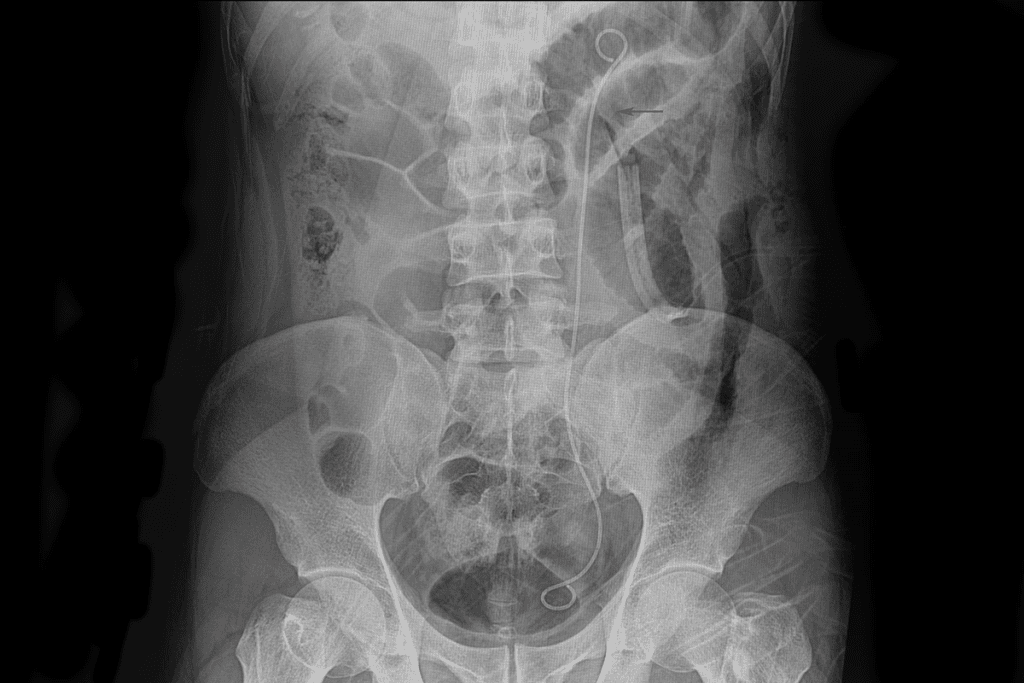

Doctors use imaging tests and other exams to find the blockage. They might use ultrasound, CT scans, or intravenous pyelography (IVP). These help see the urinary tract and find any blockages.

Other patients, like those with ureteral obstruction from kidney stones, might get pain management and hydration. In some cases, ureteral stenting is needed to keep the ureter open.

When medical treatments fail, surgery might be needed. The type of surgery depends on the cause and location of the blockage. For BPH, transurethral resection of the prostate (TURP) is common. For kidney stones, ureteroscopy with laser lithotripsy is used.

To diagnose obstructive uropathy, doctors use imaging tests like ultrasound, CT scans, or MRI. These tests help see the urinary tract and find any blockages or abnormalities.

To dislodge a kidney stone stuck in the ureter, doctors may use pain management, hydration, or surgery. Procedures like lithotripsy or ureteroscopy can remove or break up the stone.